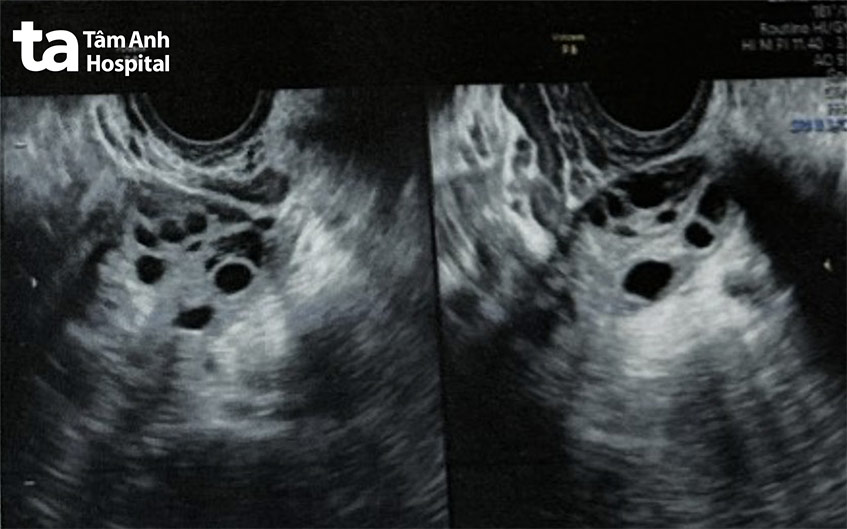

TP HCM – Chị Vân, 33 tuổi, hai buồng trứng có nhiều nang noãn nhỏ, trơn bóng như “chuỗi ngọc trai”, kinh nguyệt thưa thớt, gây vô sinh 4 năm.

Ngày 29/1, ThS.BS Giang Huỳnh Như, giám đốc Trung tâm Hỗ trợ sinh sản, Bệnh viện Đa khoa Tâm Anh TP HCM (IVF Tâm Anh TP HCM), cho biết tình trạng của chị Vân là biểu hiện của hội chứng buồng trứng đa nang (PCOS). Không có nang nhỏ nào trong số này có khả năng phát triển trưởng thành để dẫn đến rụng trứng. Đó là lý do mỗi năm chị Vân chỉ có 4-6 chu kỳ kinh nguyệt, hai lần bơm tinh trùng vào buồng tử cung (IUI) thất bại.